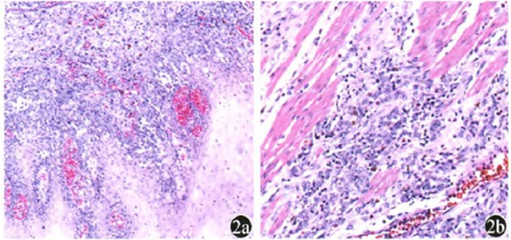

颈胸部CT示:食管胸上段占位性病变,符合食管癌改变。上消化道造影示食管上段癌。病理提示瘤细胞侵犯食管黏膜鳞状上皮,细胞异型性明显,上皮样或胖梭形,弥漫或巢状排列,浸润生长,可见色素,见图2。

图2原发性食管恶性黑色素瘤的病理学表现 苏木精—伊红染色2a 肿瘤细胞从下向上侵犯食管黏膜鳞状上皮,细胞异型性明显,上皮样或胖梭形,弥漫或巢状排列,可见色素×10 2b 肿瘤细胞侵犯食管黏膜肌层,肿瘤细胞异型性明显,上皮样或胖梭形,核仁明显,弥漫或巢状排列,浸润生长,可见色素×20